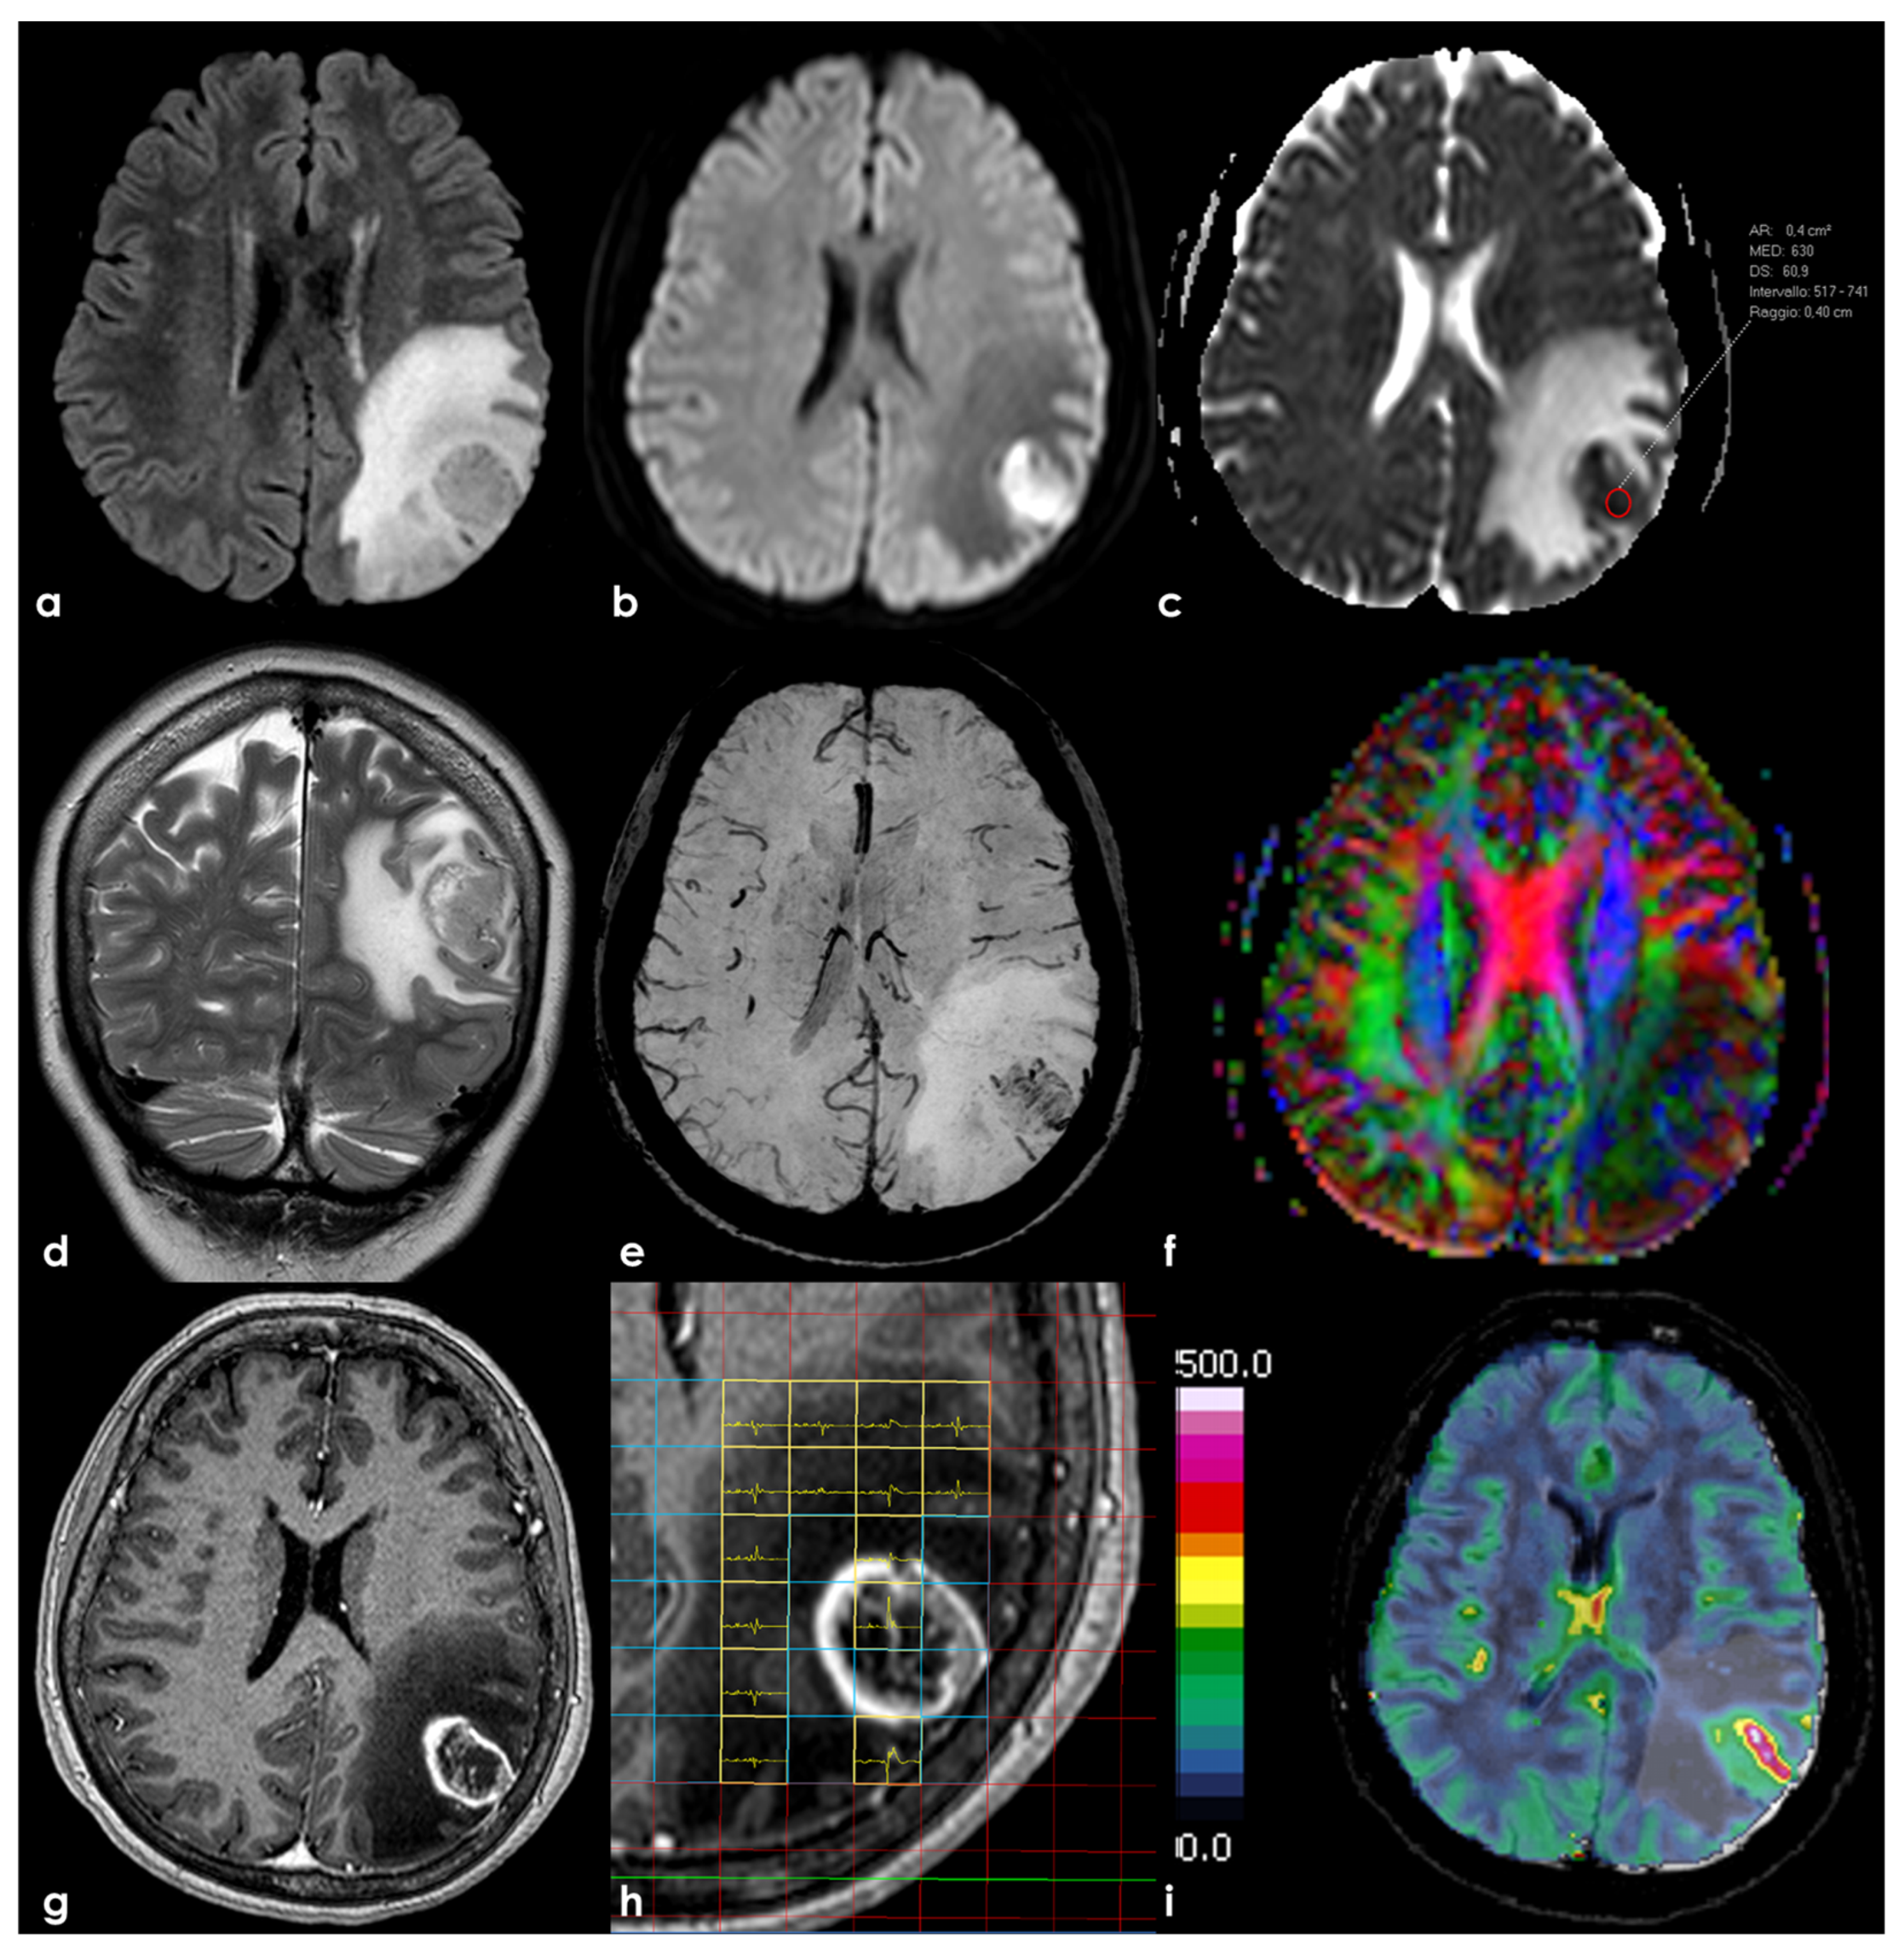

2. Biology and Epidemiology

3. Neuroradiological Pattern

3.1. Conventional MRI

3.2. Advanced MRI